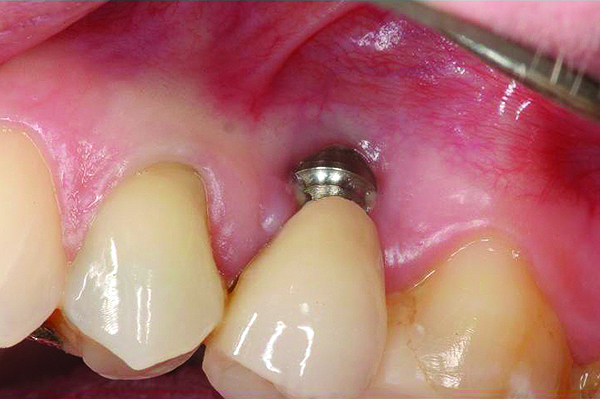

A implant restoration with a buccal dehiscence of bone and soft tissue caused by poor implant positioning, lack of keratinized tissue prior to implant placement, and soft tissue recession post implant restoration.

Figure 8

The same implant in Fig 8, 7 years following treatment, which included two autogenous connective tissue grafts and a bone augmentation surgery with a combined allograft and xenograft mixed with two biologics.

Figure 9

The implant of the patient shown in Figure 8 demonstrated all three of the red flag situations: it was placed too far buccally, had inadequate bone and soft tissue at the time of implant placement, and lost bone and soft tissue post implant placement. Correcting this required increased time, cost, and surgeries (Figure 9).

Prevention of this type of complication requires collaboration between the periodontist and the restorative dentist in the planning phase, and proper collaboration in the surgical placement, and in the restoration of the implants. No one member of the dental team can do it alone.